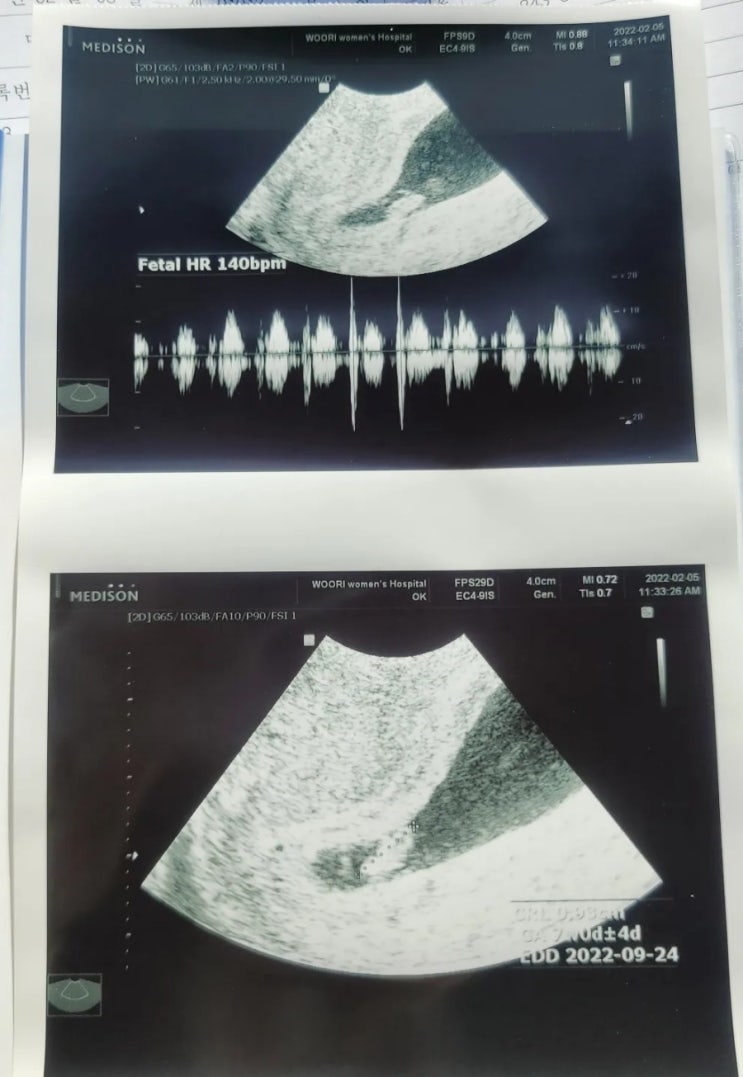

[임신7주]건강한 심장소리

오늘 정기검진(?)가는날이라서 병원에갔다왔다 사실 담주에 오라고했던거같아서..심장소리가 들릴까? 하는...